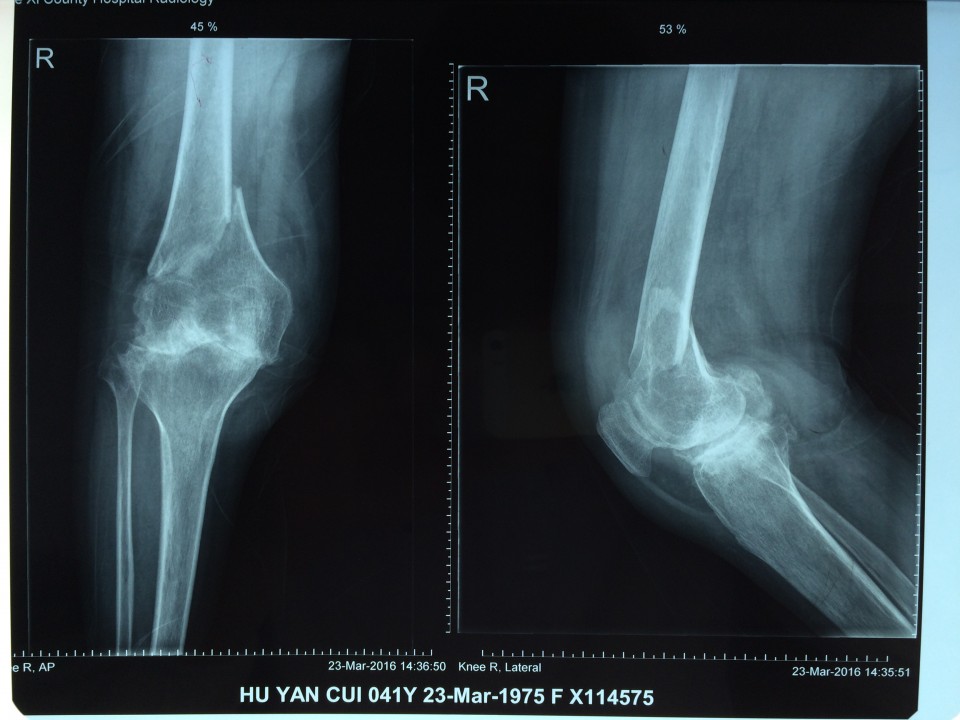

近日,我院关节中心成功完成一例重症类风关合并股骨远端骨折患者的关节置换手术。该患者长期服用激素及免疫抑制剂,骨质疏松较重;受伤前膝关节无法伸直,屈曲畸形,膝关节活动度仅15°;骨折的部位位于股骨远端,骨折处理不当,会直接影响假体的安置,造成手术的失败,因此手术难度非常大,对手术程序及逻辑性的严密度要求高。针对患者的复杂病情及手术难点,关节中心胡勇教授在风湿科、麻醉科的大力配合下,一期完成了骨折固定及人工表面全膝关节置换术。术后患者下肢力线恢复良好,骨折解剖复位,关节恢复过伸,术后5天,关节屈伸活动度恢复致40°。该手术的完成,标志着我院关节中心在复杂性关节病的治疗上又迈出了坚实的一步。